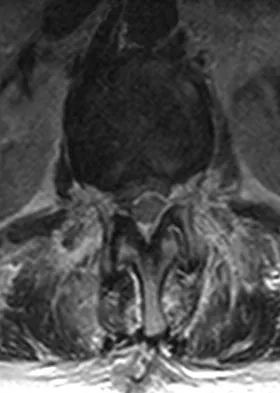

A 65-year-old man with ankylosing spondylitis has neck pain after falling back over his lawnmower, striking his thoracic spine, and forcing his neck into extension. Examination reveals subtle weakness of the intrinsics and finger flexors at approximately 4+/5. Initial management consists of immobilization in a rigid collar, and placing his head in the anatomic position. Radiographs reveal a subtle extension fracture of the lower cervical spine. Approximately 6 hours after the injury, he reports increasing paresthesias in his upper and lower extremities, and examination now shows his intrinsics are 2/5, finger flexors are 3/5, and his triceps are now weak at 4/5 on manual motor testing. In addition, his lower extremities now show weakness in both dorsal and plantar flexion of the ankle in the range of 4/5. Repeat radiographs appear unchanged. An MRI scan is shown in Figure 2. Management should now consist of

Explanation

It is not uncommon for patients with ankylosing spondylitis to sustain extension-type fractures, most typically of the cervicothoracic junction. These fractures can appear nondisplaced or minimally displaced initially, making them difficult to diagnose. Because there is no mobility between vertebrae, fractures tend to occur more like those of a transverse fracture of a long bone. In addition, the vertebral bodies are vascular and their canals are relatively enclosed, making them vulnerable to epidural bleeding. The MRI scan reveals an epidural hematoma located posteriorly on the cord; therefore, the treatment of choice is surgical evacuation and a posterior laminectomy. Because of the intrinsic instability of such fractures at the time of the laminectomy, internal fixation and stabilization with a posterior fusion is warranted. A simple laminectomy will only increase instability, and control is unlikely with halo vest immobilization. An anterior procedure will not effectively treat the problem given the location of the hematoma. Consideration can be given to methylprednisolone and observation; however, this will not eradicate the problem. Bohlman HH: Acute fractures and dislocations of the cervical spine. J Bone Joint Surg Am 1979;61:1119-1142.